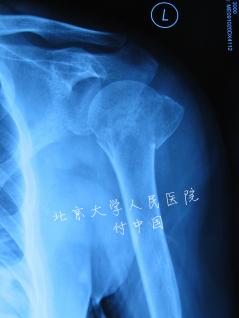

| 说明: | 外翻嵌插型四部分骨折呈现“冰激凌”样外观,肱骨头外翻嵌插,与肱骨干尚有部分骨性连接。外展嵌插型四部分骨折介于一部分骨折(微小移位)和四部分骨折之间,肱骨头成角大于45°,就由一部分骨折变为外展嵌插型四部分骨折 |

| 标题: | 外展嵌插型四部分骨折 |